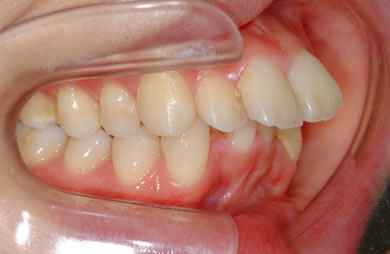

| 主訴 | 上下乱ぐい歯と出っ歯を治したい。 | ||||||||||||||||||||||||||||||||

| 治療方針 | 口元が出ていていること、がたつきが大きいことより、上下左右の第一小臼歯および親知らずを抜歯し、マルチブラケット治療を行う。抜歯した隙間を活用できるよう上顎にはインプラントアンカー(釘)を使用し、その釘より歯を後ろに移動する。 | ||||||||||||||||||||||||||||||||

| 治療内容 | 唇側矯正(シルバー)、矯正用スピードインプラント、ハイブリッドセラミックインレー2本 | ||||||||||||||||||||||||||||||||